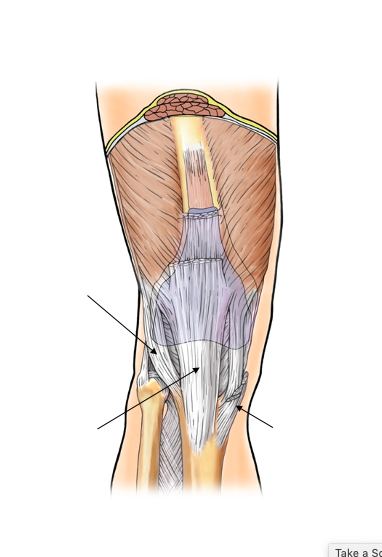

which is muscle A?

semitendinosus muscle (bc superior portion is almost aporneurotic)

which muscle is A&B?

what are origins of A&B?

Bicep femoris

A - long head - comes from common hamstring - ischial tuboristy

B - short head - comes from posterior aspect of femur, laterally

where do the Biceps femoris, Semimembranosus & Semitendinosus attach ? (medially or laterally)?

Biceps femoris: laterally

Semimembranosus: medially

Semitendinosus: medially